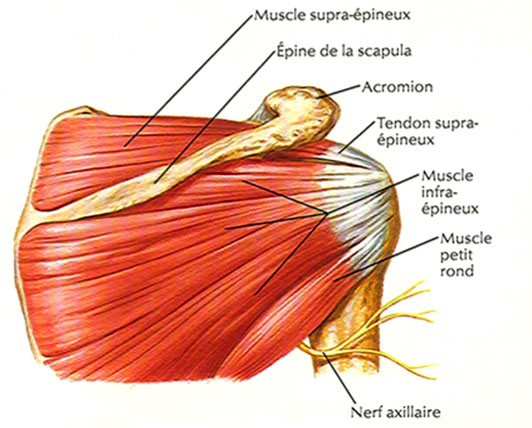

Les douleurs à l’épaule (ou omalgies) font partie des motifs les plus fréquents de consultation en médecine générale et rhumatologie. L’épaule est une articulation très complexe, et de nombreuses structures la composant peuvent être le siège de blessures ou de douleurs. Ainsi, l’épaule est composée de deux espaces de « glissement » et de 3 articulations :

Lorsqu’on bouge le bras, ces différentes articulations interviennent de manière simultanée. Dans la grande majorité des cas, les douleurs d’épaule sont liées à une pathologie de la « coiffe des rotateurs », une sorte de « capsule » de tendons composée de la convergence des tendons de quatre muscles. Il ne faut pas tarder à consulter un médecin ou un rhumatologue en cas d’omalgie, afin de maintenir autant que possible une bonne mobilité du bras.

Les douleurs d’épaule peuvent traduire de multiples pathologies : infections, tumeurs, pathologies systémiques, affections neurologiques, etc. Dans la majorité des cas, toutefois, ces douleurs sont liées à une atteinte de la coiffe des rotateurs (surtout après 50 ans). Les causes peuvent aussi, bien sûr, être traumatiques : entorses, tendinites, blessures, fracture, etc. Lorsqu’il n’y a pas d’antécédent de traumatisme, l’épaule douloureuse est souvent liée à une tendinite « dégénérative » de la coiffe des rotateurs. La coiffe des rotateurs peut aussi être le siège de calcifications. Elle peut aussi se rompre totalement ou partiellement. Les autres causes les plus fréquemment rencontrées sont :